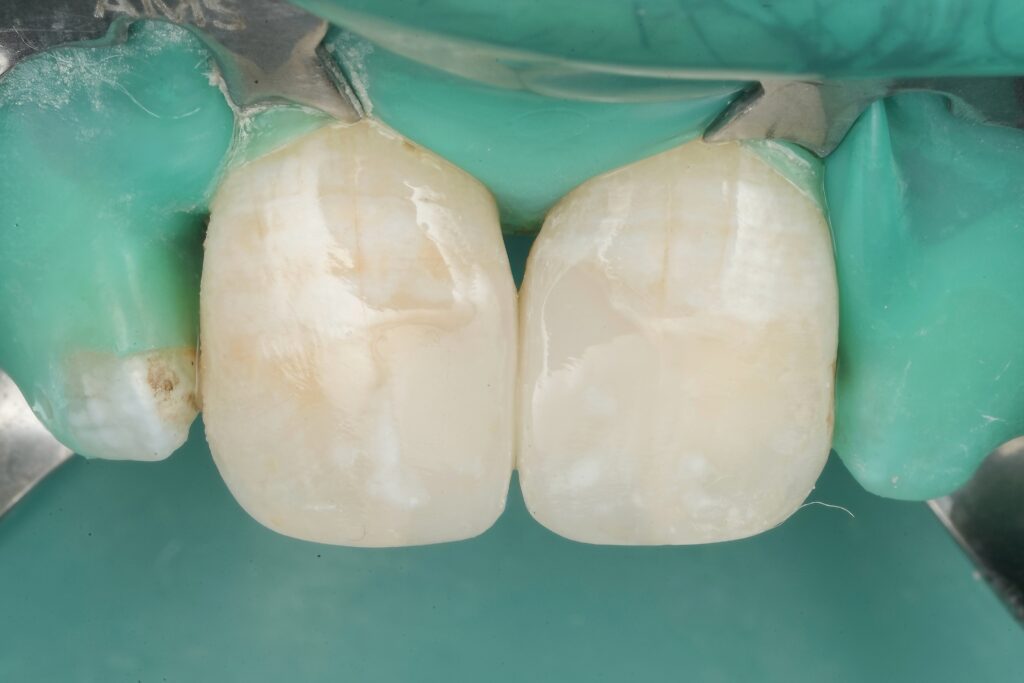

2) Rubber dam isolation (non-negotiable)

Rubber dam was placed before any definitive steps. Adhesive dentistry is moisture-sensitive; contamination reduces bond quality and increases risk of marginal staining, post-op sensitivity, and early breakdown.

Clinical tip: clamp stability + floss ligatures + teflon/caulking as needed. Your “bonding field” should look like a controlled laboratory.